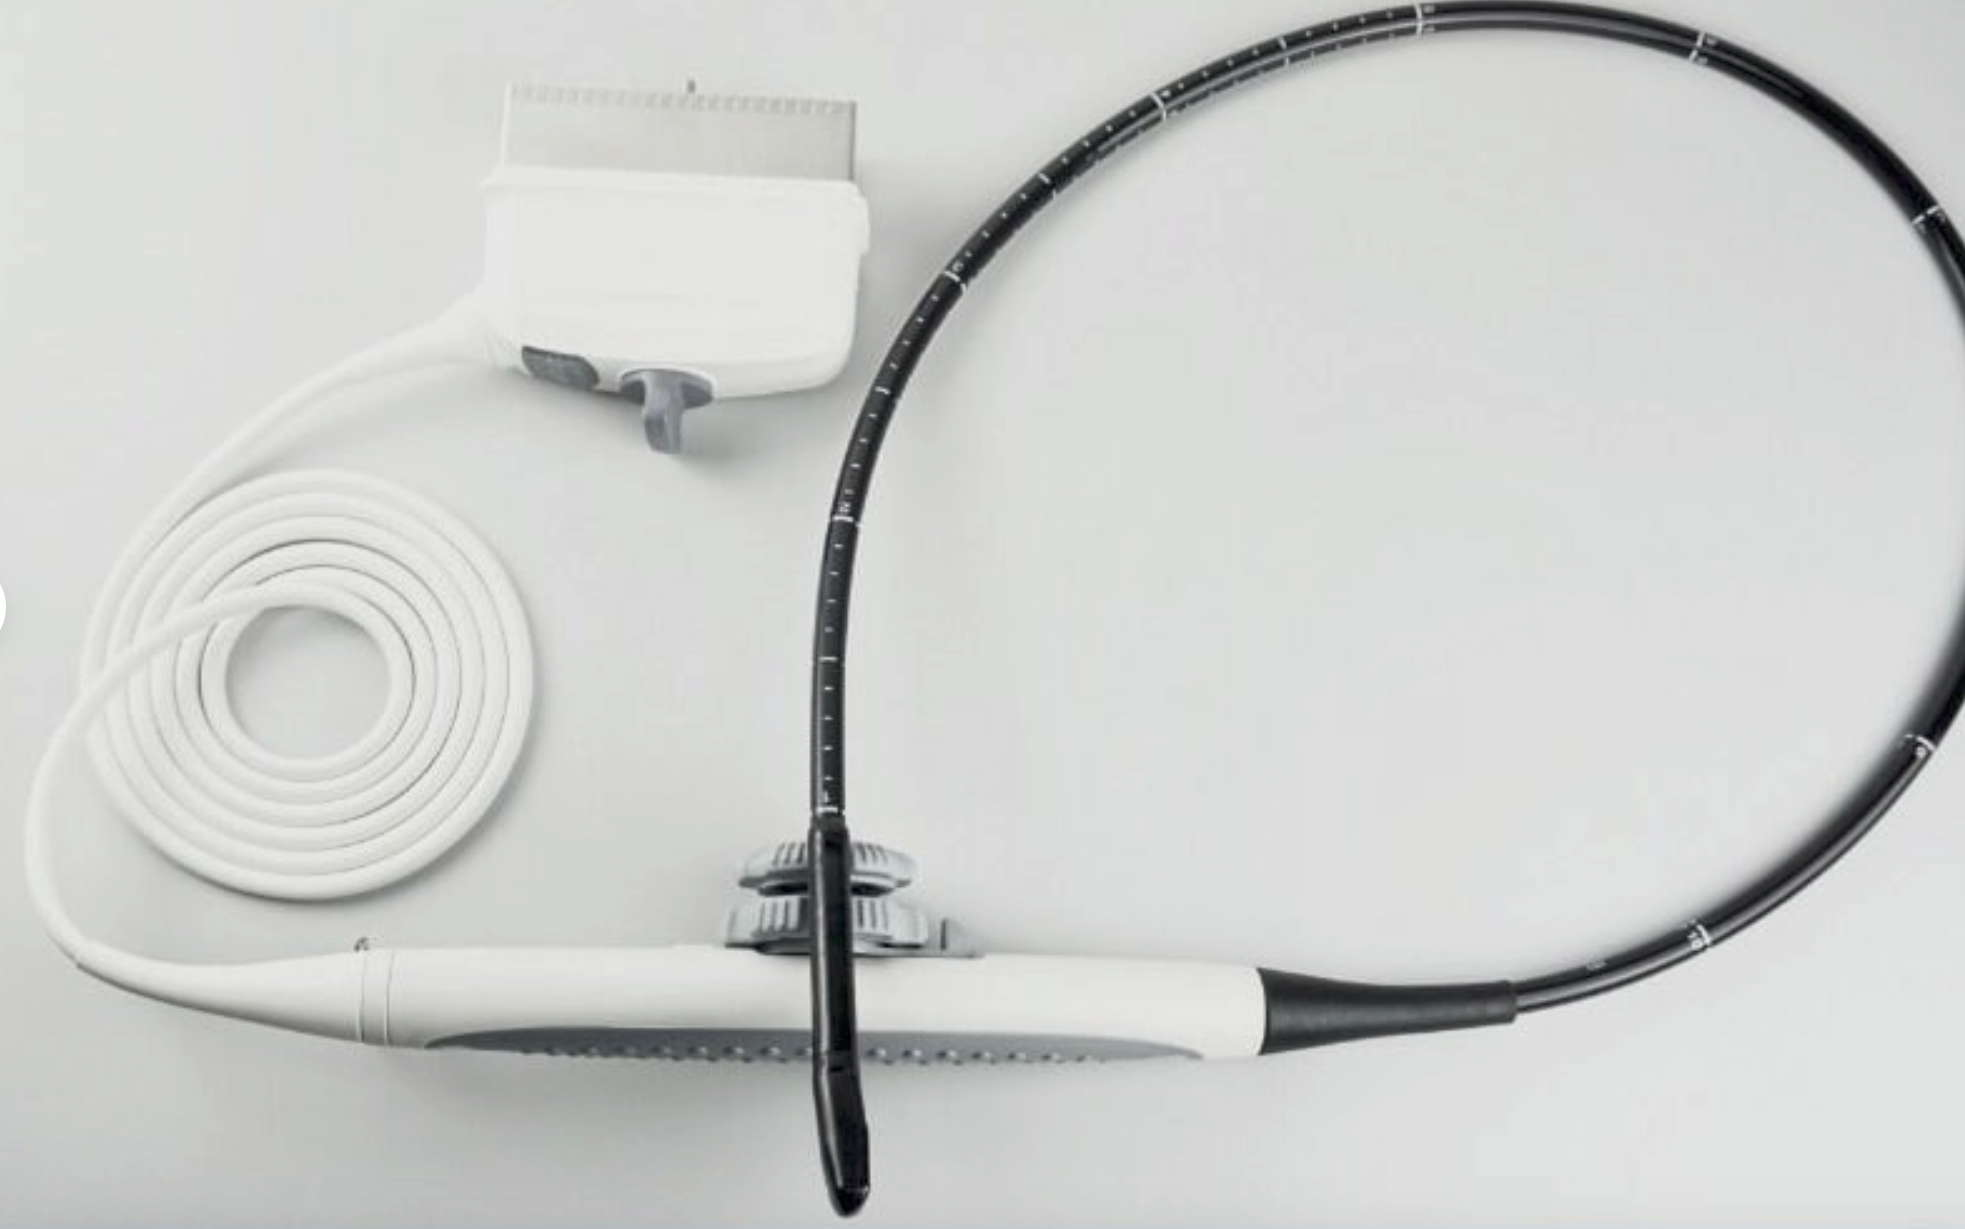

Versatile Probes for Comprehensive Diagnostics

The laptop ultrasound scanner comes with three types of probes: convex, linear, and transvaginal. These versatile probes make it suitable for various applications, whether it's obstetrics, gynecology, or general imaging. This versatility means clinicians can perform diverse examinations effectively, which is crucial for accurate diagnoses. So whether you're in a hospital or a private practice, this ultrasound scanner meets all your imaging needs.